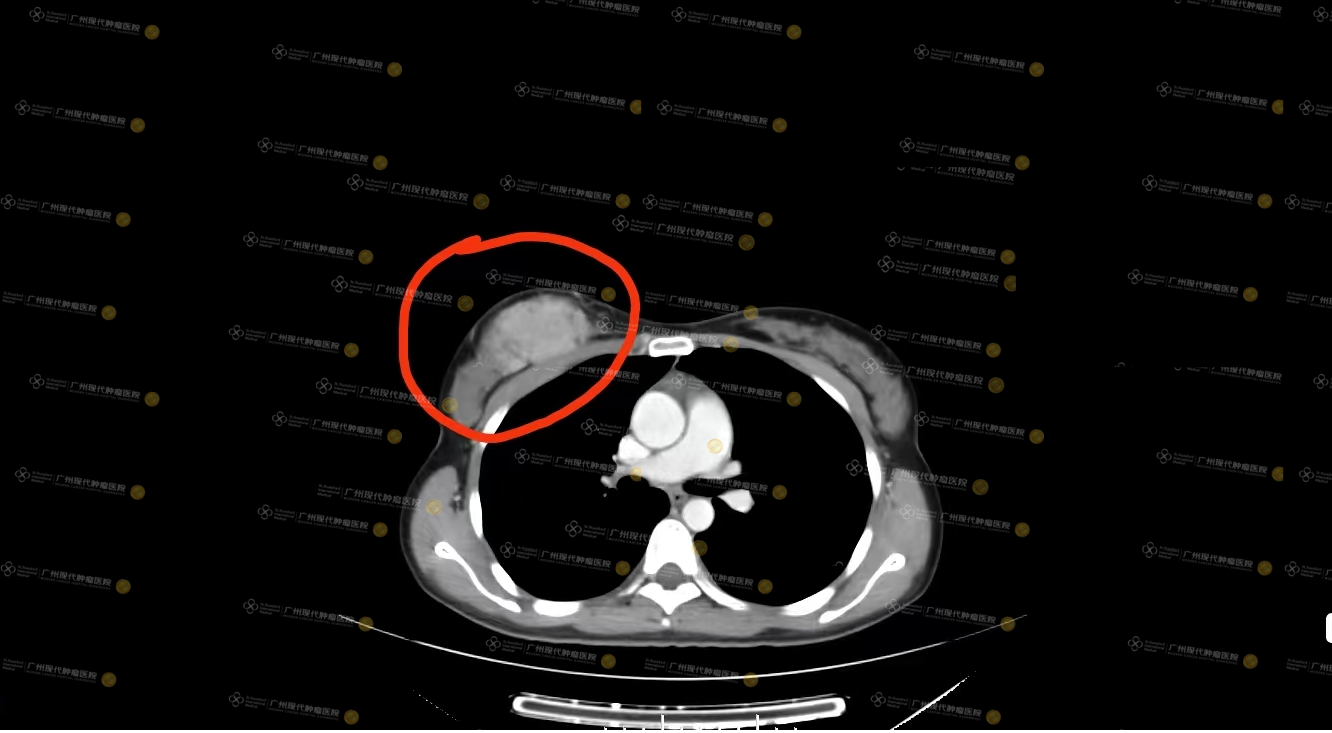

(28/8/2018, CT lần đầu khi Loh Nina nhập viện)

Kết quả điều trị thực sự rất đáng mừng. Sau điều trị hệ thống, đánh giá hiệu quả lần thứ tư cho thấy khối u ở vú phải của Loh Nina đã thu nhỏ 50%–60%, đạt trạng thái đáp ứng một phần (PR). Đến lần tái khám cuối cùng vào tháng 1/2019, qua đánh giá hình ảnh học, ổ tổn thương nguyên phát và các tổn thương di căn hạch nách của Loh Nina đều đã đạt trạng thái đáp ứng hoàn toàn về mặt lâm sàng (CR).

So sánh hình ảnh: lần nhập viện đầu năm 2018 VS lần tái khám cuối tháng 1/2019 — phần lớn tế bào ung thư đã mất hoạt tính